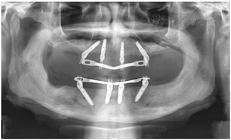

(2)2015年9月行拔牙及上颌种植手术。口腔局部阿替卡因肾上腺素注射液浸润麻醉,拔除上下颌余留牙,搔刮清理拔牙窝内肉芽组织,见43、44、47区牙槽骨缺损(图4),修整下颌牙槽嵴,黏膜瓣复位,4-0可吸收缝线缝合下颌术区。16~26区牙槽嵴顶近远中向切开牙龈黏膜、翻瓣,平整牙槽嵴顶骨嵴,分别于12、15、22、25区定点,逐级备洞,15区倾斜植入Nobel Speedy 4 mm×15 mm种植体,12、22、25区骨质量较差,为获得良好初期稳定性选用Nobel Active种植体,12区植入Nobel Active 5 mm×13 mm种植体,22区植入Nobel Active 4.3 mm×13.0 mm种植体,25区倾斜植入Nobel Active 5 mm×13 mm种植体,种植体初期稳定性均达到35 N·cm,旋入复合基台,修整牙龈,缝合。术后拍摄全颌曲面体层片(图5)。

(5)术后复查:术后1个月、5个月复诊,上下颌过渡义齿咀嚼功能较戴用可摘义齿明显改善,面型及发音正常。X线全颌曲面体层片显示种植体骨结合良好(图10)。

种植修复后1、2、4年随访X线全颌曲面体层片显示种植体周围骨结合良好(图13A~C),患者对修复体美观及咀嚼功能效果满意。修复后6年(2022年8月)随访X线全颌曲面体层片及根尖片显示种植体周骨结合良好,上前牙区种植体颈部骨吸收约1 mm(图13D、图14)。取下上下颌义齿,清理义齿组织面滞留菌斑,清洁复合基台并检查基台中央螺丝稳定,清洁义齿组织面,戴回上下颌义齿(图15)。患者口腔卫生宣教,指导正确刷牙,使用冲牙器冲洗义齿与牙龈间缝隙,嘱6个月复查、维护。